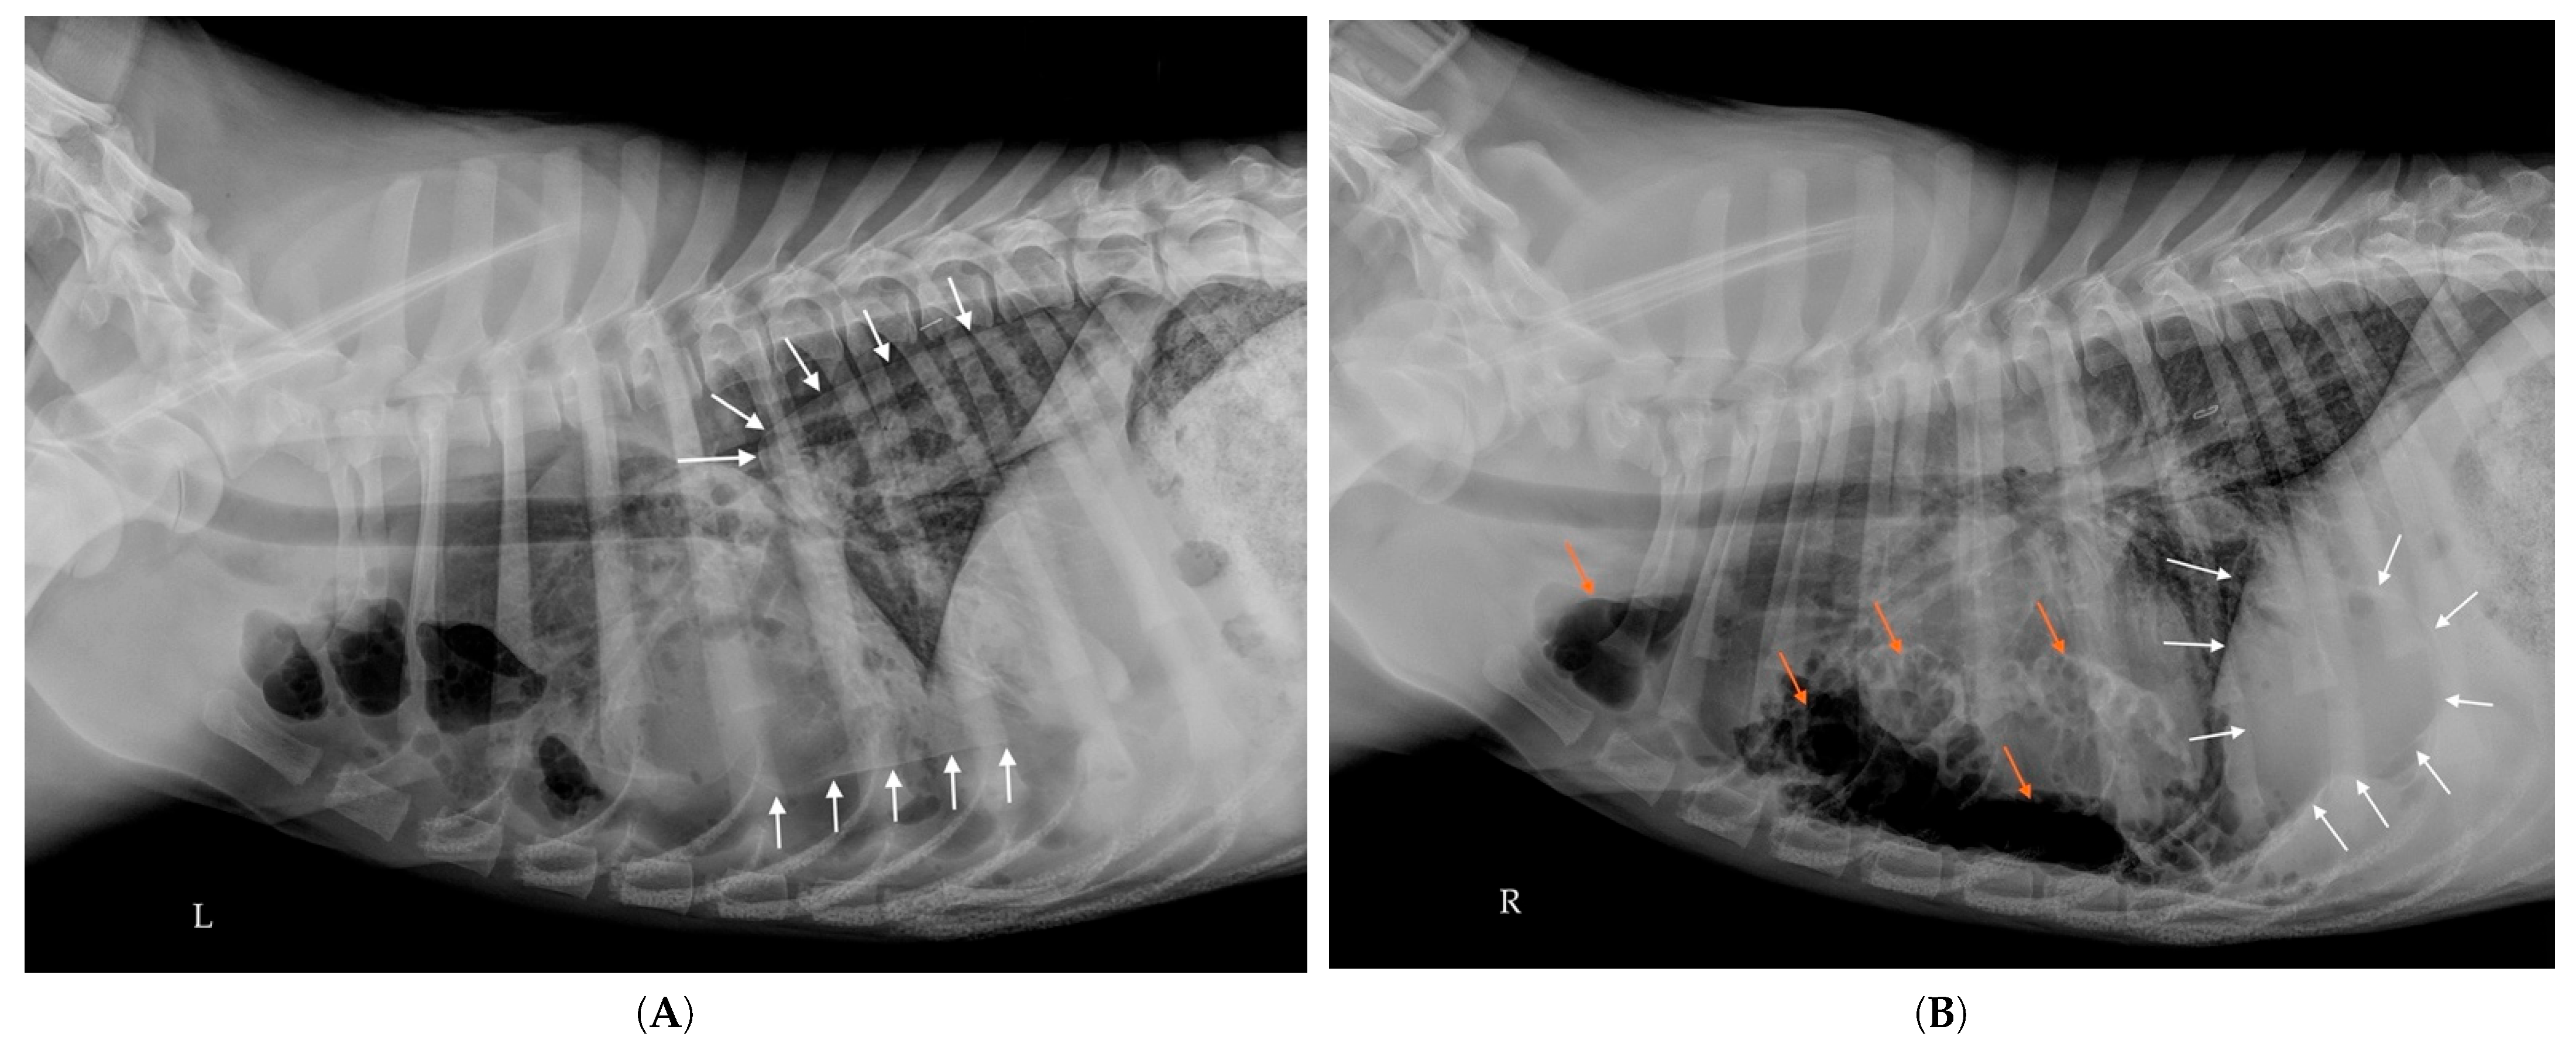

2.8. Follow-Up Radiographs

2.9. Thoracostomy Tube Placement